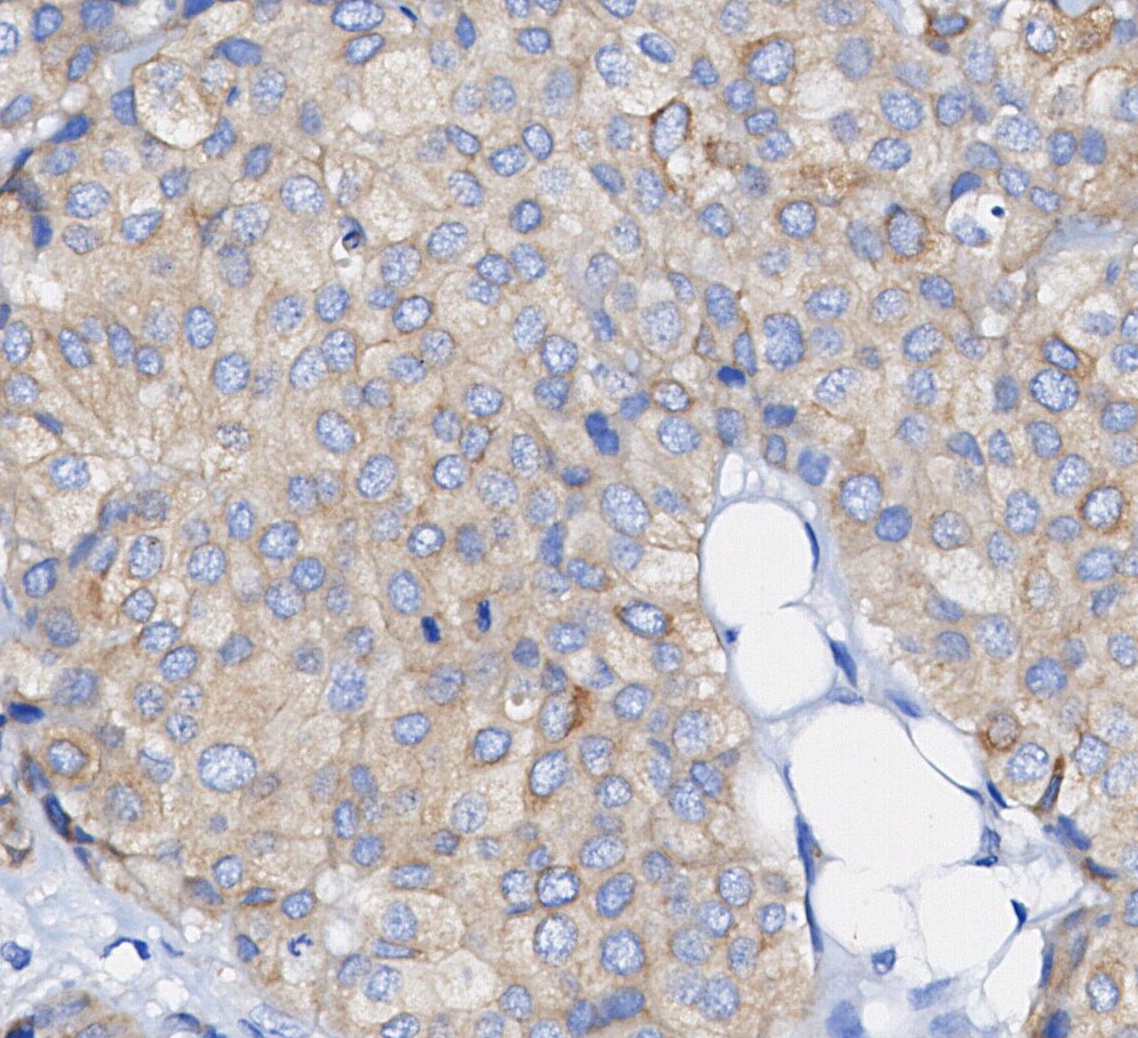

• Immunohistochemical analysis of formalin fixed paraffin embedded human breast cancer tissue with F0225 at 1/100 dilution.